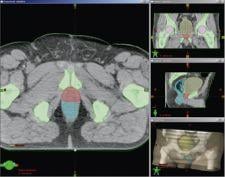

The new Smart Segmentation automatic contouring feature is reportedly the first fully automatic tool that uses intelligent software to identify and outline, within diagnostic images, organs and other structures to be irradiated or protected during treatment. The first version of the Smart Segmentation tool performs automatic contouring of tumors and surrounding anatomy in the thorax and in the male pelvis. Additional anatomical sites will be added in the near future.